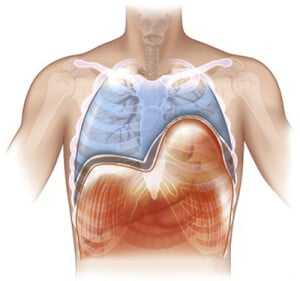

Диафрагма (diaphragma от греч. — перегородка), или грудобрюшная преграда — это куполообразная перегородка, которая разделяет грудную и брюшную полости. Выделяют центральную сухожильную и краевую мышечную части диафрагмы. Сокращаясь и расслабляясь диафрагма принимает участие в акте дыхания.

Релаксация диафрагмы - одностороннее стойкое высокое расположение диафрагмы, сохраняющей свою непрерывность и прикрепление в обычных местах.

В основе заболевания — повреждение диафрагмального нерва, при котором диафрагма расслабляется и не сокращается (т.е. наступает её релаксация). Так как в брюшной полости положительное давление, а в грудной клетке в большей части отрицательное, то органы брюшной полости давят на релаксированный купол диафрагмы. Таким образом, купол диафрагмы поднимается выше обычного, сдавливая собой соответствующее легкое. Часто заболевание так и называют — релаксация купола диафрагмы.

Рентген. Рентгенологическое исследование является решающим в диагностике релаксации, при этом определяются следующие симптомы:

- стойкое повышение уровня расположения соответствующего купола диафрагмы до 2 - 5 ребра;

- в горизонтальном положении диафрагма и прилежащие к ней органы брюшной полости смещаются кверху;

- контур диафрагмы представляет собой ровную, непрерывную дугообразную линию.

Нередко выявляется ателектаз нижних отделов легкого и смещение средостения.

Релаксация диафрагмы рентген (левый купол)